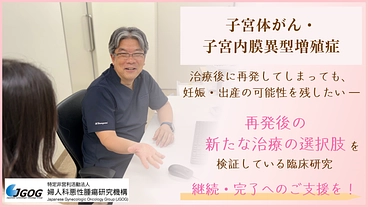

子宮体がん再発後も、妊娠の可能性を守るための挑戦。臨床研究の継続へ

- 現在

- 10,052,000円

- 支援者

- 327人

- 残り

- 22日